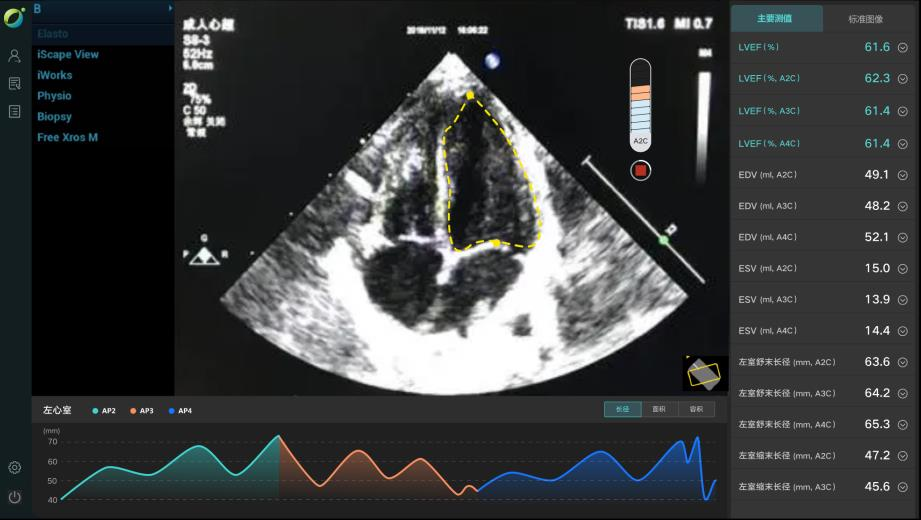

AI智能影像輔助診斷技術(shù)具有對醫(yī)學(xué)影像進行圖像篩查、病灶分類、定位、檢測、圖像分割等優(yōu)勢。它能夠在海量的醫(yī)學(xué)影像中準(zhǔn)確、快速且客觀地篩選出特定疾病的影像,確定圖像中病變區(qū)域的空間位置,檢測需要識別圖像中所有的目標(biāo)并且確定其類別,并在醫(yī)學(xué)影像中分割標(biāo)注出不同的組織和器官,計算圖像中的血流量等代謝信息。

除上述肺結(jié)節(jié)人工智能篩查示例外,目前已形成了全鏈路人工智能產(chǎn)品解決方案,在影像、超聲、病理方面都與AI智能影像輔助診斷技術(shù)高效結(jié)合,幫助醫(yī)院實現(xiàn)自動化、高精度的影像診斷檢查,讓患者在疾病篩查中實現(xiàn)早期診斷、預(yù)測、治療、療效評估與監(jiān)測。